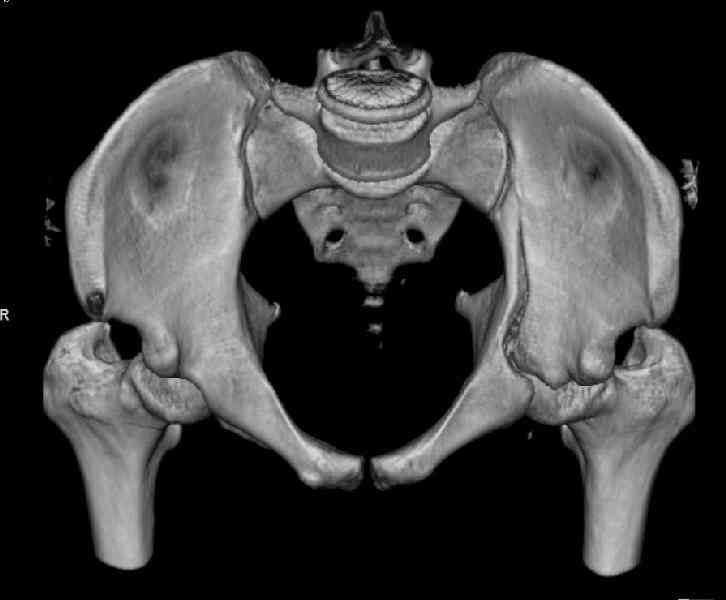

Мужчина 33 лет получил травму в шахте (придавило вагонеткой) 6 недель назад. Изолированное повреждение вертлужной впадины.

В местной больнице отлежал несколько недель на вытяжении. После выписки амбулатрный травматолог направил в институт. На сегодня, похоже, уже имеется неправиильное сращение. См. картинки.

Dear all, A male 23 y.o. injured 6 weeks ago - mine trauma, impacted by a carriage. Isolated injury of the acetabulum. At the initial hosptial was on bed traction some weeks. After discharge visited anotheк orthopaedic surgeon who referred him to our unit. To date looks like a malunion. Images attached. The question is about what to do now - either leave it as is or perform open reduction? If the latter what approach, reduction manoeuvres and fixation would you advice? Thx in advance!